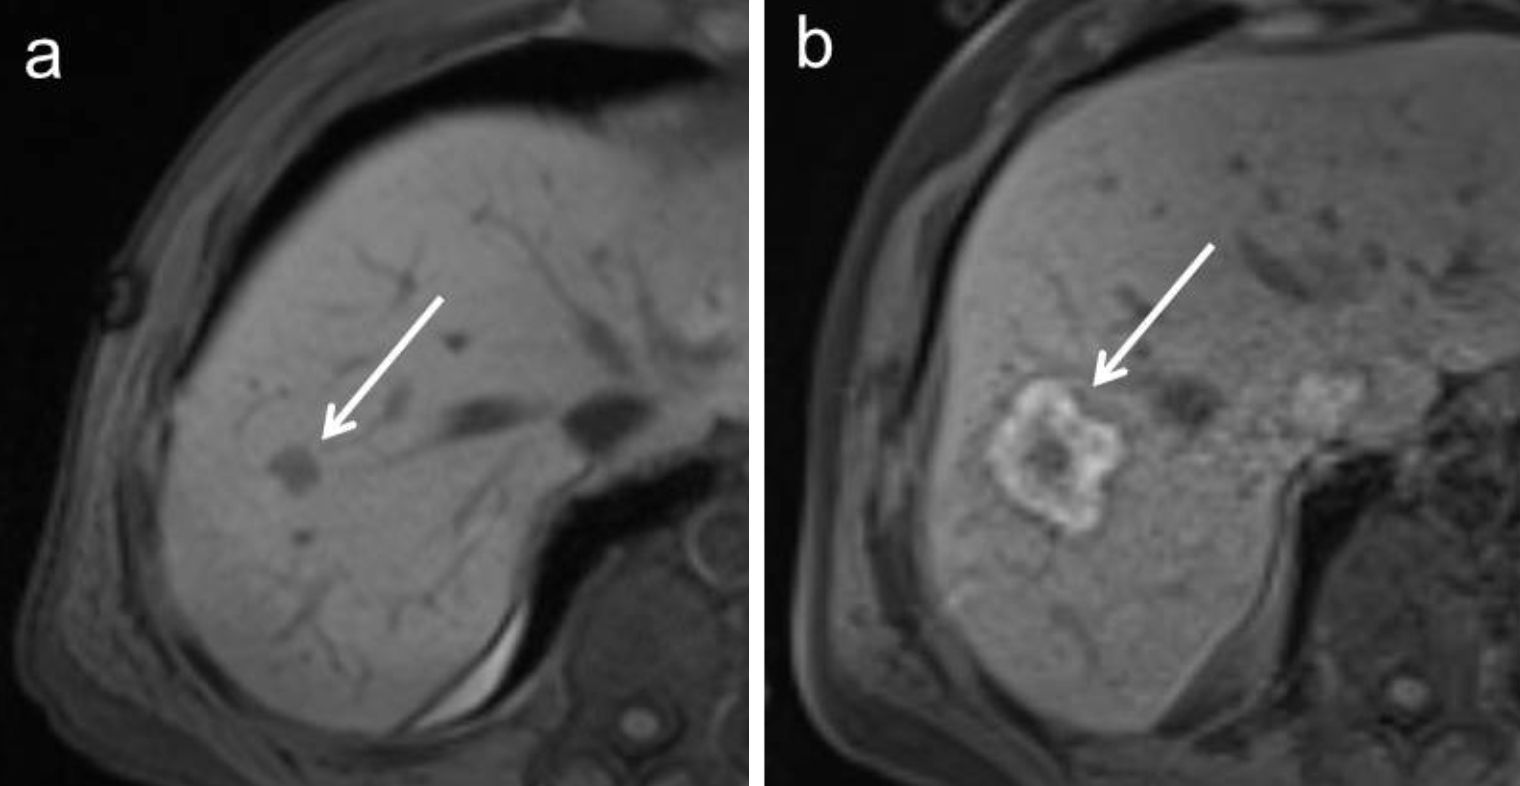

Das Institut für Diagnostische und Interventionelle Radiologie der Uniklinik Tübingen ist eines von wenigen Einrichtungen weltweit, an dem Thermoablationen von Leber- und Nierentumoren unter MRT-Steuerung durchgeführt werden. Die MRT als Bildgebungsmodalität bietet einige interessante Vorteile für perkutane Thermoablationen wie zum Beispiel eine zuverlässige Beurteilung des Therapieeffektes (siehe Abbildung 1), eine freie Wahl der Bildgebungsebene, eine genaue Darstellung auch kleinster Tumore und zeitlich hoch aufgelöste Sequenzen zur sicheren (und strahlungsfreien) Positionierung von Thermoapplikatoren. Das Ziel der Arbeitsgruppe „Interventionelle MRT“ ist die Erforschung der Möglichkeiten MRT-gesteuerter Eingriffe sowie die Untersuchung und Weiterentwicklung neuer Techniken.